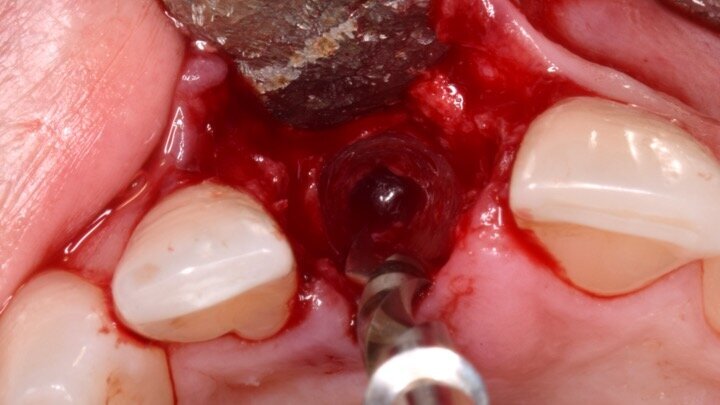

Figura 1. Atrofia de más del 50% de la pared vestibular en el diente 11 con infecciones de repetición de varios años de evolución.

Figura 4. Exodoncia del diente.